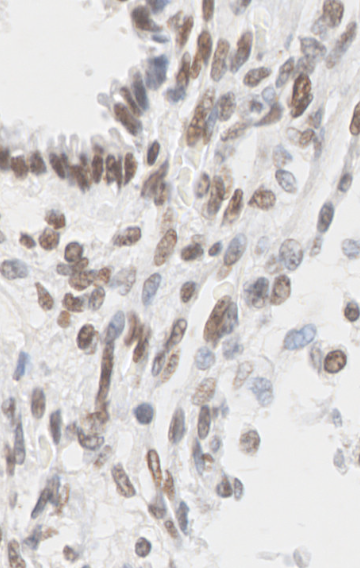

3.5 Digital pathology

Digital pathology integrates the acquisition, management and interpretation of pathology information generated from digitalized tissue stainings present on glass slides (citep \@BBN(Jahn, Plass, and Moinfar, 2020)). The process starts with high-throughput scanning of glass slides on dedicated slide scanners. The obtained images can be further used for diagnostics, web-based consultations with other expert pathologists in tumour boards, quantitative analysis, and secure archival of pathology data as well as for the development of machine learning tools for tumour classification. However, the application of the listed operations is only valuable upon high image quality and a cost-effective scanning process. Image quality is highly dependent on scanner type and scan settings.Furthermore, image size is considerably large, with one image usually comprising 1-2 GB, such that data storage and data access represent additional challenges for digital pathology. In this light, optimizing the digitization process through the establishment of quantitative criteria for image quality standards would greatly contribute to efficient workflows and manageable image usage.

3.5.1 Visualization Problem

Currently, the slide scanner operators personally set the parameters on the machine to optimize the scanning procedure. At first, the scanning device performs a low-resolution overview scan in an automated manner. The operator is required then to select a dedicated field of imaging for high-resolution imaging with a 40X objective, followed by the application of focus points to the selected scan area. The distribution of these focus points can either be performed in an automated manner by the scanner software (up to 9 focus points), or manually by the operator (if more than 9 focus points are desired). The choice of how many focus points are used is usually based on the operator’s personal preference, where setting focus points manually is highly time-consuming. Furthermore, each focus point increases the required scanning time for slide digitization, thus adding to the time investment of pathologists at the machine while at the same time limiting the number of slides that can be scanned within one day. However, image quality correlates with the ability of the pathologists to provide an accurate diagnosis to their patients. The diagnosis can have life-impacting consequences, such as the choice of the best treatment options for tumour patients based on tumour subtype classification by the histopathological evaluation of tissue sections. Thus, automated IQA for different choices of focus points would be helpful to design a standardized, cost and time effective workflow while providing medical experts with images of reasonable quality for accurate diagnostics.

3.5.2 Data

The data presented in this study have been acquired from digital images of immunohistochemistry stainings that were performed on archival tissue obtained from the neurobiobank of the Division of Neuropathology and Neurochemistry at the Medical University of Vienna. Stainings have been performed according to standard procedures (citep \@BBN(Guo et al., 2024; Schwaiger et al., 2023)). Figure 11 (a)-(c) shows a tumour biopsy of a gliosarcoma patient stained for the astrocyte marker GFAP (brown signal, cytoplasmic localization) and counterstained with Hematoxylin (blue signal, nuclear localization). Figure 3 (d)-(e) shows fetal cerebellar tissue stained for the epigenetic mark H3K27me3 (brown signal, nuclear localization) and counterstained with Hematoxylin (blue signal, nuclear localization). The stained sections have been digitalized on a NanoZoomer 2.0-HT digital slide scanner C9600 (Hamamatsu Photonics, Hamamatsu, Japan). The corresponding software NPD.Viewer2 was used to export the scanned images to tiff files. Here, we performed individual scans of a selected imaging area with different numbers of focus points. We chose either 1, 3 or 9 focus points while not changing the spatial settings for the selected field of interest. The image with 9 focus points, allowing the highest resolution, serves as the reference image.

Refer to caption

(a) Reference

(b) (18.6, 0.80, 0.10)

(c) (23.6, 0.91, 0.33)

(d) Reference

(e) (22.9, 0.81, 0.11)

(f) (27.0, 0.87, 0.22)

Figure 11: Data acquired with a slide scanner and 9 (a)(d), 3 (b)(e) and 1 (c)(f) focus points. The image with 9999 focus points serves as a reference here. PSNR and SSIM misjudge the tiny spatial misalignment and therefore favor the blurry images with 1 focus point. LPIPS is able to ignore these spatial misalignments.

FR-IQA mismatches

Although the spatial settings for the selected scan area of interest were not changed during the experiment, the physical performance of the scanner showed slight spatial deviations of the selected area between individual scans and thus does not allow for high spatial accuracy during re-scanning processes. PSNR and SSIM fail to correctly assess the images in Figure 11 as they are very sensitive to that kind of spatial misalignment. Whereas the scan with 3 focus points corresponds much better to the higher-quality reference as the blurred scan with 1 focus point, see (b) and (e) versus (c) and (f), both measures incorrectly judge the blurred scan as the better one. This wrong judgement due to a tiny spatial change is very problematic in the respective framework as it is impossible to guarantee completely exact spatial alignment, even if no other settings had been changed during the scanning process. LPIPS, not being so sensitive to small spatial deviations, is able to correctly judge the rank of quality here.